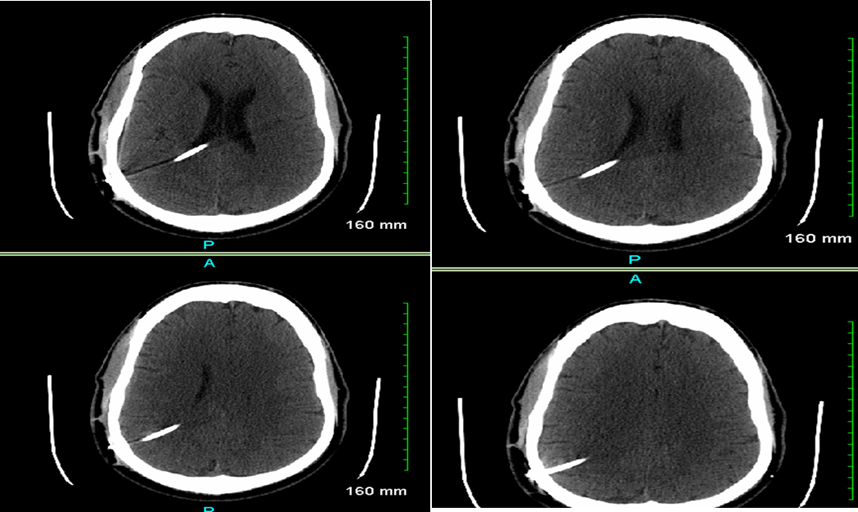

We report a case of a 51-year-old male presented to the neurology clinic with intermittent dizziness, blurred vision, chronic left sided weakness and numbness. Further workup by brain MRI unearthed increased intracranial pressure secondary to impaired CSF drainage. He was previously diagnosed with Arnold Chiari type I malformation for which ventricle-peritoneal shunt (VPS) was performed in 1994 (Figure 1). Following this, ensuing imaging or evaluation for shunt revision was never attempted. During routine follow up, he complained of abdominal pain and subsequent work up revealed microscopic hematuria. A CT scan of abdomen and pelvis unearthed a peritoneal cerebrospinal fluid (CSF) pseudocyst which is compressing the ureter and causing hydronephrosis (Figure 2). The probable causes of peritoneal pseudocyst including infection and adhesions was thoroughly investigated with appropriate investigations. Subsequently, he was referred for surgical resection of abdominal pseudocyst. During surgical exploration, a large peritoneal CSF containing pseudocyst with adhesions was identified. Furthermore, the pseudocyst was irregular in shape, lacked proper epithelial lining and had an ill-defined border. Complete resection of CSF pseudocyst was performed and VPS was removed and repositioned in another abdominal quadrant. Following surgery, patient signs and symptoms were completely resolved. He was advised to have a regular follow up of VPS periodically to detect shunt malfunction and associated complications.

Figure 1. CT head with and without contrast. A right posterior parietal approach shunt extending though the lateral ventricle with its tip at the posterior midline in the upper third ventricle. Ventricular system appears to be decompressed. The intracranial and extracranial shunt tube appears to be normal.